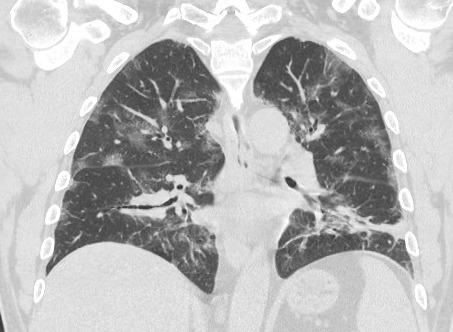

Of the total 47 cases, there were 16 (34.0%) case reports with only a CT, two (4.2%) with only a chest radiograph, and 26 (55.3%) with both a CT and a chest x-ray. Ground glass opacities were noted for 33 (69.8%) of patients with a CT (Figure 1). Among case reports with a CT published, crazy paving was noted by the radiologist in 10 (20.9%) of the case reports (Figure 2) and thickening of the interlobular septa was noted by the radiologist in 14 (30.2%) of the case reports.